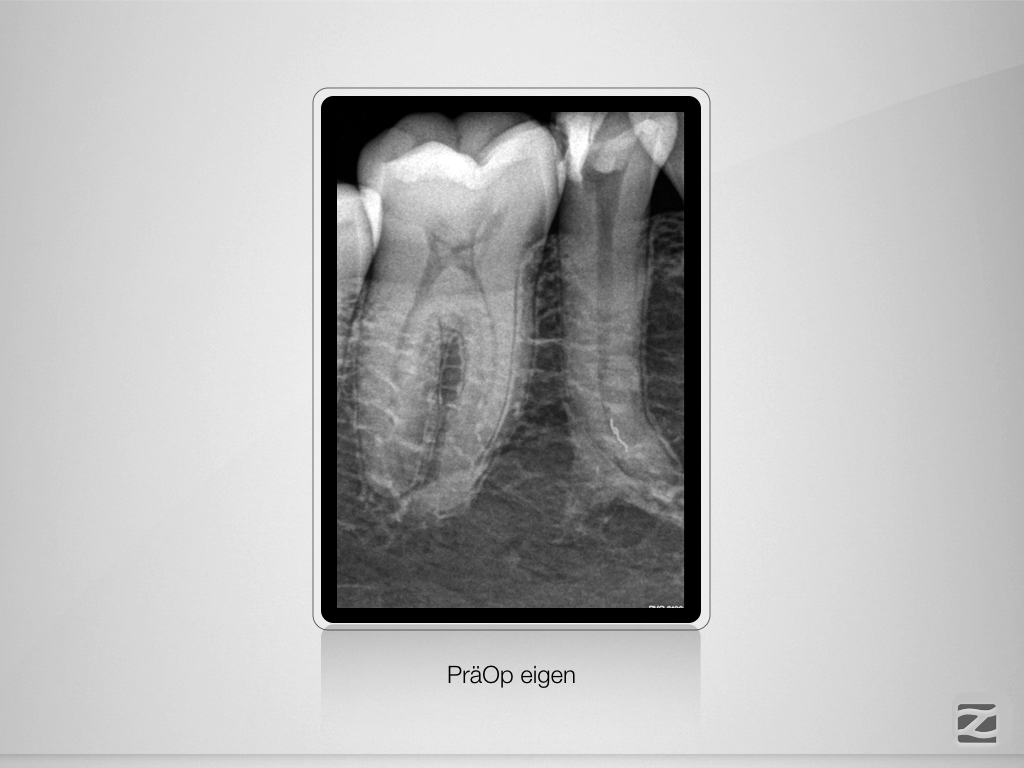

Prämolaren sind (nicht) einfach!